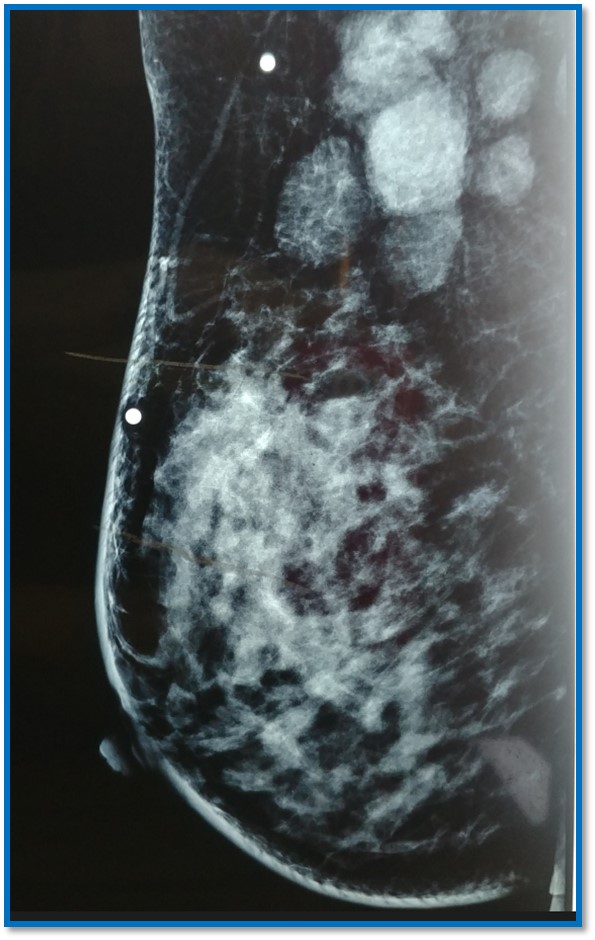

Mastografía:

Se realizó Biopsia con aguja de corte con Dx de carcinoma ductal infiltrante SBR 8 en etapa clínica IIIC recibió quimioterapia neoadyuvante. Se realizó mastectomía con linfadenectomía ipsilateral.